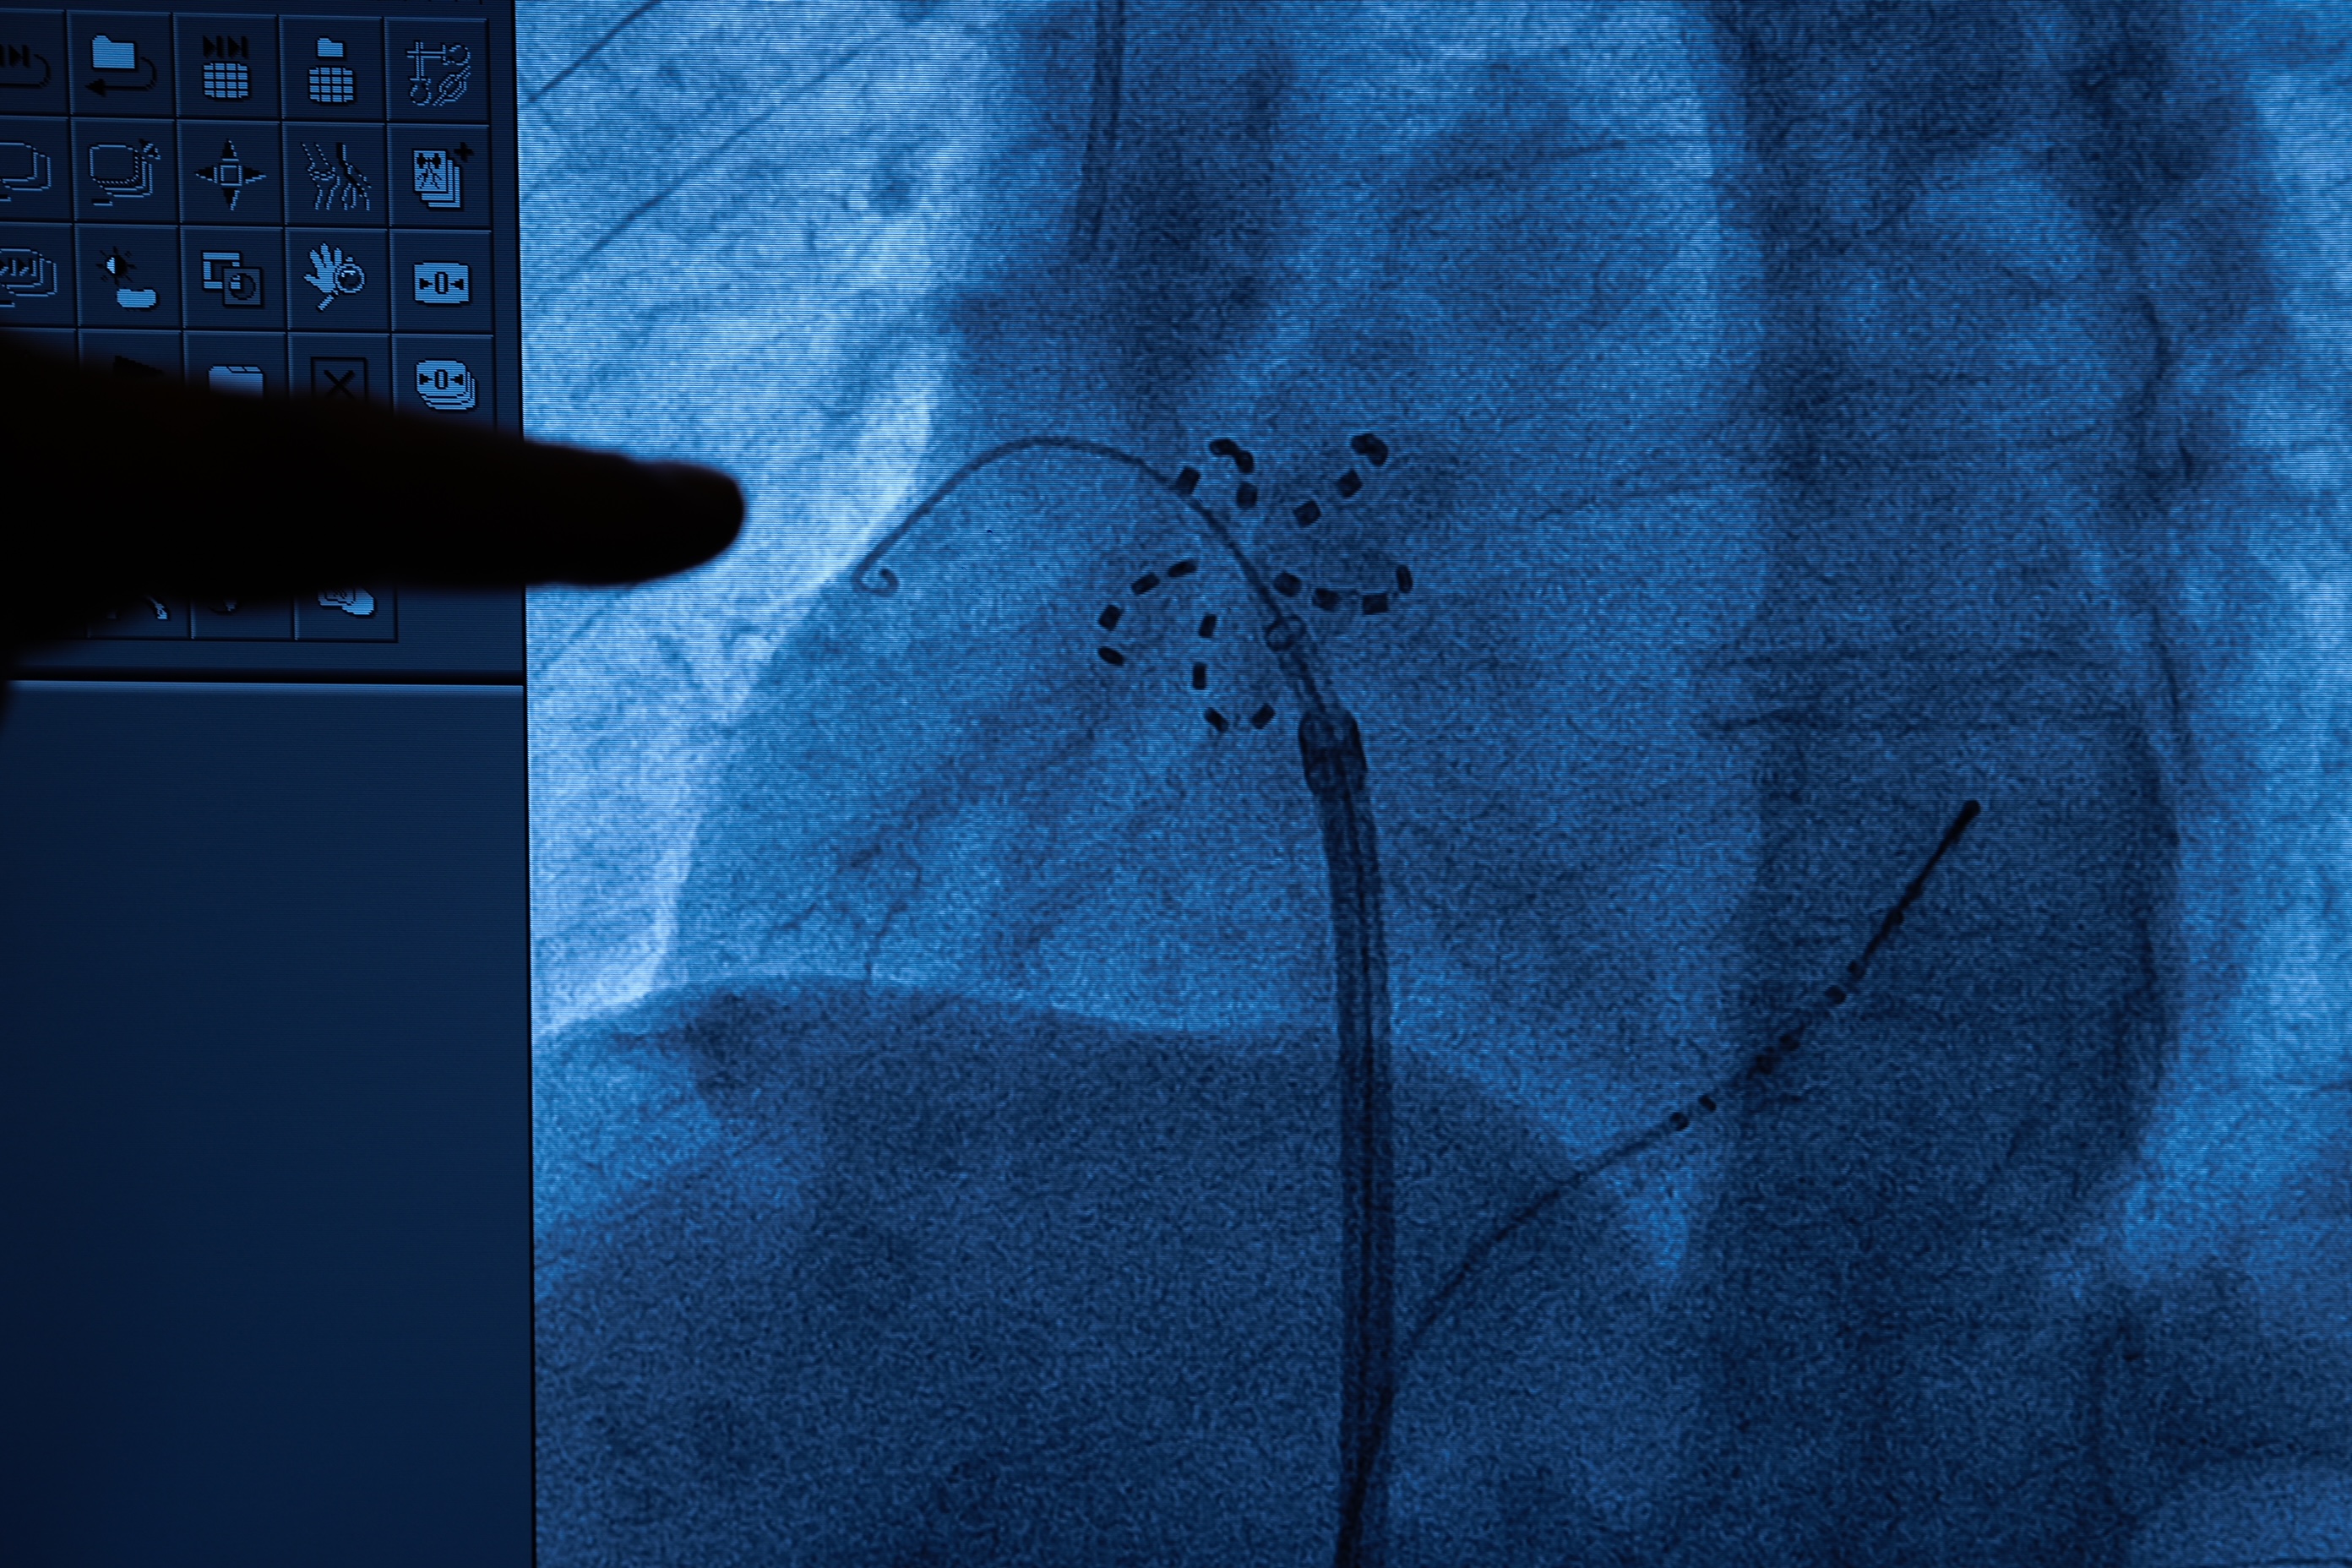

Yeni nesil tedavi yöntemi hakkında önemli bilgiler paylaşan Prof. Dr. Kılıçaslan, “Daha önce radyo frekans ve kriyoablasyon yöntemleri kullanıyorduk. Radyo frekans ve kriyoablasyon ile yapılan ablasyonlarda kalbin çevresindeki dokular da etkilenebiliyor ve nadir de olsa akciğer damarlarında daralma, yemek borusunun ve solunum sinirinin hasarlanması gibi ciddi komplikasyonlar görülebiliyordu. PFA ile bu önemli risklerin hiçbiri görülmüyor. PFA yöntemi, kasıktan damar yoluyla ilerletilen kateterle uygulanıyor. Kateter ucundaki elektrot, problemli dokulara yüksek frekanslı elektrik dalgası gönderiyor ve bu dokuların elektriksel aktivasyonu ortadan kalkıyor. Böylece ritim bozukluğu tedavi edilmiş oluyor” dedi.